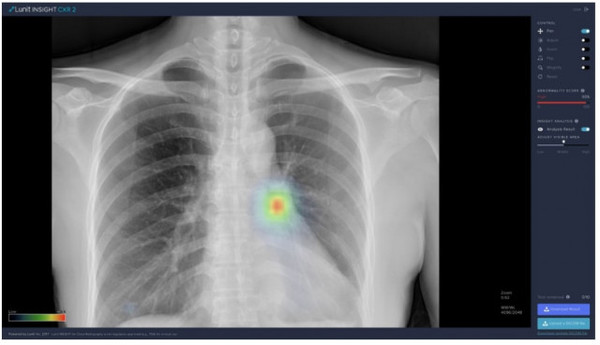

해당 연구를 비롯해 본 사업에서 사용되는 루닛의 폐 질환 진단 보조 인공지능 소프트웨어인 ‘루닛 인사이트 CXR’은 국내 식약처 및 유럽 CE 인증을 받아 국내외 대형 및 종합병원을 비롯한 150여 곳 이상의 헬스케어 기관에서 사용되고 있다. 최근에는 식약처 지정 혁신의료기기에 폐 질환 진단 관련 제품으로는 최초로 선정된 바 있다.